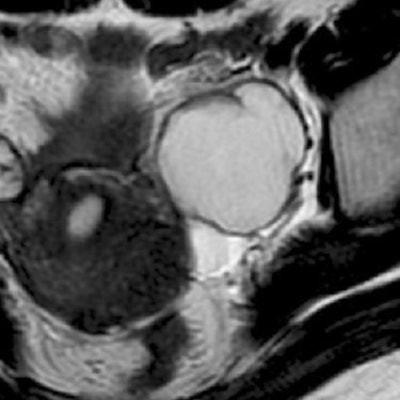

The shading sign, caused by the T2 shortening in an adnexal cyst, is an MR feature of endometriosis and is helpful for making the differential diagnosis, Takeuchi explained. In addition, the hemosiderin-laden macrophage deposits in the cyst wall are another pathologic feature of endometrial cysts, which results in signal voids on SWI.

According to the results, signal intensity of the cysts was lower at 3-tesla MRI than at 1.5-tesla based on visual inspection. The cyst-to-muscle SIR on 3-tesla imaging was 2.04 ± 0.90 versus 4.72 ± 2.34 on 1.5-tesla MR. The shading sign was seen on 3-tesla MR, but not on 1.5-tesla MR, in two lesions.

| Endometrial cyst with the shading sign on T2-weighted 3-tesla MRI (above), which was not demonstrated on T2-weighted 1.5-tesla MR (below). Images courtesy of Dr. Mayumi Takeuchi. |

In addition, signal voids caused by hemosiderin deposition in the cyst were seen more readily on 3-tesla SWI than on 1.5-tesla MRI. Finally, in an e-mail to AuntMinnie.com, Takeuchi said that using 3-tesla MRI did cut down on the exam time (eight minutes and 24 seconds versus nine minutes and 47 seconds at 1.5-tesla).